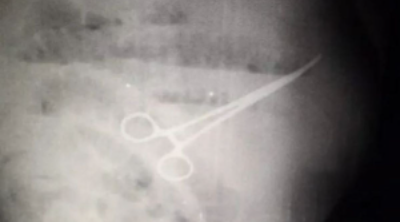

Old  Default Bệnh nhân tử vong do bác sĩ để quên kéo trong bụng

Ông Ivan Chavez đã đến Bệnh viện Đại học Maracaibo, ở thành phố lớn thứ hai của Venezuela, để khám dạ dày. Sau đó ông được các bác sĩ kết luận phải tiến hành phẫu thuật để cắt túi thừa bị viêm. Ca mổ được cho là đã diễn ra thuận lợi.

Tuy nhiên vài hôm sau, ông Chavez bắt đầu cảm thấy đau bụng, khó ăn uống và đi vệ sinh. Mặc dù các bác sĩ đã kê cho ông nhiều phương pháp điều trị khác nhau tuy nhiên, cảm giác khó chịu không giảm bớt.

Bốn ngày sau các nhân viên y tế quyết định tiến hành chụp X-quang và phát hiện có một chiếc kéo đã bị bỏ quên trong dạ dày của bệnh nhân. Ông Chavez lại thêm một lần nữa phải tiến hành phẫu thuật khẩn cấp tuy nhiên ông đã tử vong sau đó 5 ngày, gia đình nạn nhân đã đổ lỗi cho các bác sĩ vì làm việc cẩu thả.

Tuần trước, bác sĩ Freddy Pachano Arenas, người làm việc tại bệnh viện, đã thông báo trên Twitter rằng các đồng nghiệp của ông là Gerardo Núñez và Luis Gómez đã được thả sau khi liên quan đến cái chết của

Ông Pachano khẳng định "không thể đổ lỗi cho ai đó cố ý giết người trong một hành động tìm cách cứu mạng sống của một người khác".

Tại thời điểm báo cáo, một nhân viên bệnh viện vẫn bị tạm giam nhưng cơ quan chức năng không tiết lộ người này có sớm được trả tự do hay không cũng như vai trò của người này trong ca phẫu thuật của ông Chavez.

Bác sĩ Pachano cũng khẳng định cái chết của Chavez không phải do chiếc kéo bị bỏ quên trong bụng tuy nhiên gia đình nạn nhân cho rằng các bác sĩ đã che giấu tình trạng thực sự của ông với họ và cố giả vờ như thể mọi thứ diễn ra bình thường, không có sơ sót nào xảy ra. Họ cũng nói rằng nhân viên bệnh viện chỉ thông báo về cái chết của Chavez hai tiếng sau khi ông qua đời.

Chưa có thông tin vê việc người nhà ông Chavez có đâm đơn kiện ai tại bệnh viện hay không.

Hệ thống chăm sóc sức khỏe của Venezuela được cho là đang bị tê liệt do cuộc khủng hoảng kinh tế kéo dài và nghiêm trọng của đất nước. Do điều kiện khó khăn của đất nước đã buộc hàng nghìn bác sĩ và y tá phải di cư ra nước ngoài trong những năm gần đây.